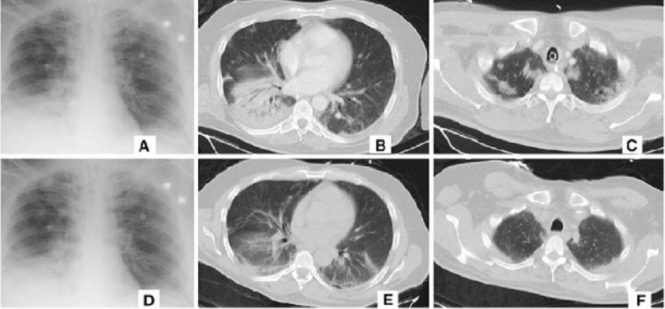

Am aflat recent şi că PC-urile cele mai puternice din lume au fost puse la treabă pentru a căuta un leac pentru Covid-19. Pe partea de AI, gigantul tech Alibaba a dezvoltat un sistem care poate detecta Coronavirusul la pacienţi. Noul sistem face un soi de scanare CT (tomograf) care poate detecta boala în doar câteva secunde, în locul celor 15 minute necesare pentru ca un medic să depisteze virusul. Alibaba afirmă că metoda sa are acurateţe de 96%. Pentru a putea antrena acest sistem pe bază de AI, el a primit o sumedenie de imagini şi date bazat pe 5000 de cazuri de Covid-19 din China.